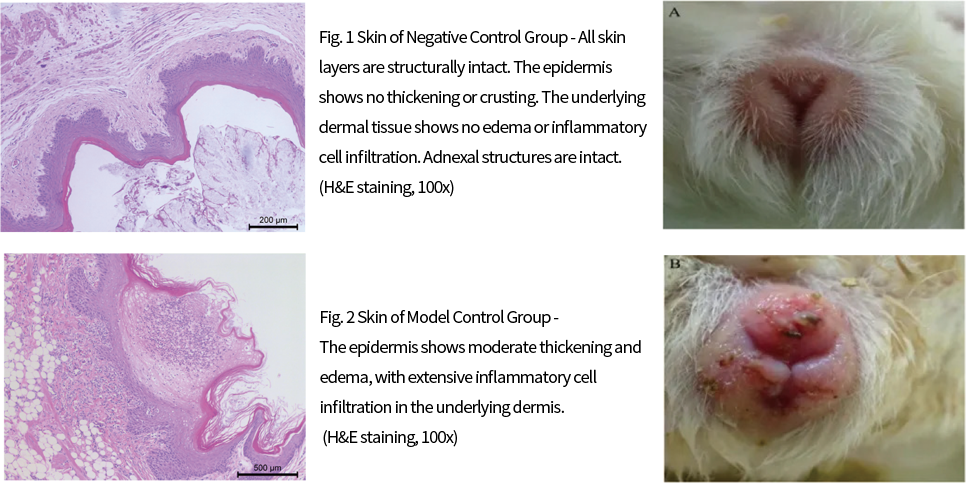

◆ Animal Models for Skin Diseases

Pressure Ulcer Model

A self-made pressure device (with good repeatability, simple and safe experimental operation and device) simulates pressure ulcer (decubitus ulcer) wounds of varying degrees in skin tissue by controlling pressure and time on a specific pressure area, forming pressure ulcers at different stages. It investigates wound healing and contraction rate, partially simulating the clinical characteristics of pressure ulcer occurrence.

Pressure Ulcer Modeling and Manifestations